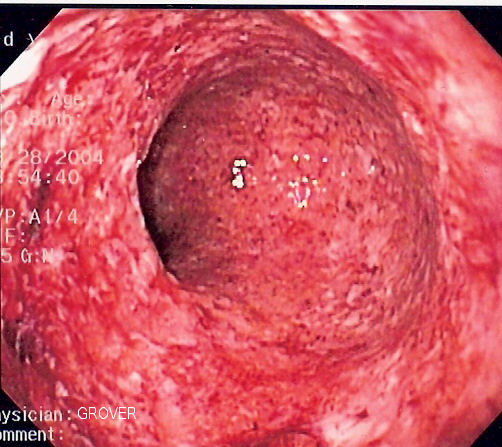

Zdroj: Autor Samir, Endoscopic image of severe Crohn's colitis showing diffuse loss of mucosal architecture, friability of mucosa in sigmoid colon and exudate on wall., licence CC-BY-SA-3.0.

Obr. 5. Crohnova choroba